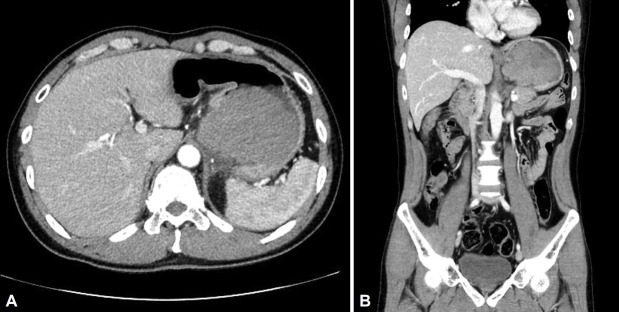

一名48岁男性来我院评估黑黑症。腹部计算机断层扫描(CT)显示胃底和上半身有一个内生增强肿块(约9厘米)。CT未见其他器官转移。内窥镜检查发现一个大肿块,伴有渗出物和表面出血的迹象。肿块的形状类似于上皮下肿瘤,约50%的粘膜脱落。内窥镜超声检查显示高回声扩散和大夫棒状无回声病变排列在整体低回声肿块内。患者行全胃切除术并淋巴结清扫,诊断为未分化多形性肉瘤,无淋巴结转移。未分化多形性肉瘤是一种高度侵袭性软组织肉瘤,主要累及四肢,很少发生胃。它通常是无症状的,但往往迅速增长。表现前一年的内窥镜成像无显著性。我们报告一例胃未分化多形性肉瘤,表现为快速生长的上皮下肿瘤。快速生长的胃上皮下肿瘤患者在鉴别诊断时应考虑胃肠道间质肿瘤以外的恶性肿瘤。

A 48-year-old man presented to our hospital for evaluation of melena. Abdominal computed tomography (CT) revealed an endophytic contrast-enhanced mass (approximately 9 cm) in the gastric fundus and upper body. CT showed no evidence of metastasis to other organs. Endoscopic examination revealed a large mass accompanied by an exudate and signs of surface hemorrhage. The shape of the mass resembled that of a subepithelial tumor, and >50% of the mucosa was peeled off. Endoscopic ultrasonography revealed hyperechoic spreading and dotor rod-shaped anechoic lesions arranged within an overall hypoechoic mass. The patient underwent total gastrectomy with lymph node dissection and was diagnosed with undifferentiated pleomorphic sarcoma without lymph node metastasis. Undifferentiated pleomorphic sarcoma, a high-grade aggressive soft tissue sarcoma, predominantly involves the extremities and rarely the stomach. It is usually asymptomatic but tends to grow rapidly. Endoscopic imaging performed a year prior to presentation was unremarkable. We report a case of a gastric undifferentiated pleomorphic sarcoma that presented as a rapidly growing subepithelial tumor. Malignancies other than a gastrointestinal stromal tumor should be considered in the differential diagnosis in patients presenting with a rapidly growing gastric subepithelial tumor.